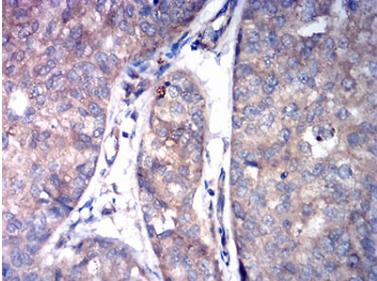

ASGR2 Mouse Monoclonal antibody[2C6D1]

IHC    1/200 - 1/1000